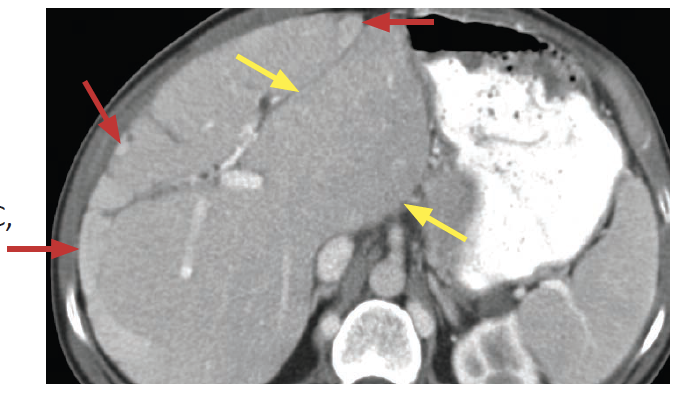

Dx?

Pseudocirrhosis

Macronodular liver contour from multiple scirrhous hepatic metastases (mimic cirrhosis)

MCC is treated breast cancer

Capsular retraction is charactersitic when present